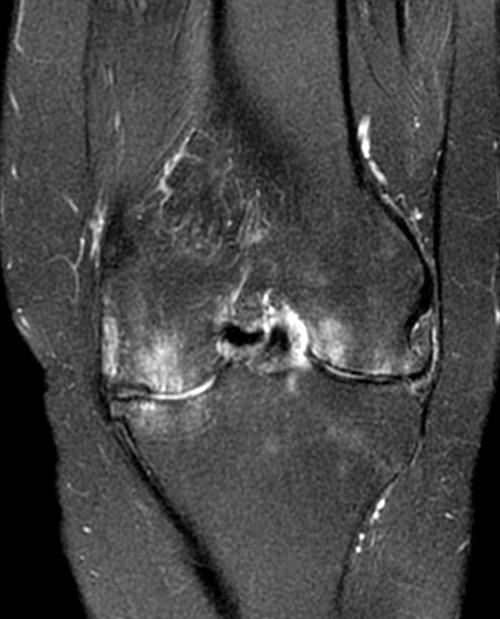

Knee Rheumatoid Arthritis Severe Synovitis Mri Stock Photo Image of Rheumatoid Arthritis Diagnosis Mri Moreover, the paper aims to illustrate the significance of mri and. There are three main types of ra imaging tests used in diagnosing and monitoring disease. Modern imaging modalities allow accurate detection of both inflammation and damage in rheumatoid arthritis (ra) joints. It can also assess all the joints in your body at once. Mr imaging of rheumatoid arthritis. Aditya. Rheumatoid Arthritis Diagnosis Mri.